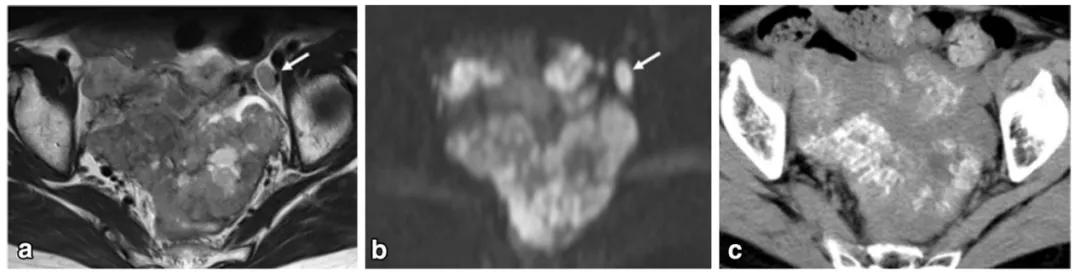

女,18 岁,卵黄囊瘤(右侧),AFP 升高。T2WI 示卵巢实性为主肿物(图 a),内见低信号纤维血管分隔(白箭),实性成分 DWI 呈高信号(图 b),增强扫描明显强化(图 c),内见无强化坏死区(箭头)。